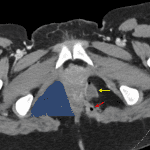

- Multiple peripherally-enhancing tubular fluid and gas containing structures along the left aspect of the anus communicating with a collection anteriorly measuring 2.5 x 1.7 cm

- Additional perianal collection on the right measuring 1 x 1 cm

- Perianal fistulae and abscesses

Findings concerning for perianal fistulae and abscesses, left greater than right. In conjunction with the finding of submucosal fat deposition in the terminal ileum (a sign of prior inflammation), these findings are particularly concerning for inflammatory bowel disease, particularly Crohn disease.